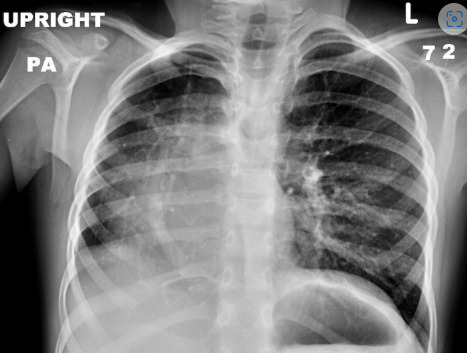

The X-ray shows _____ sign which is suggestive of partial anomalous pulmonary venous return.